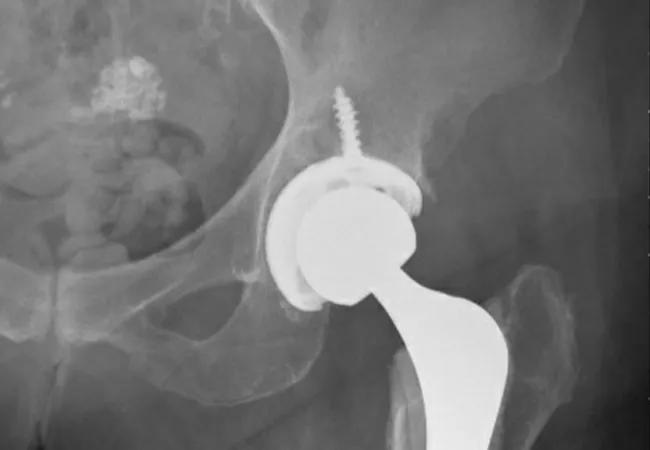

In his own practice, Dr. Piuzzi frequently sees good outcomes of THA in older patients. He recently treated a 90-year-old woman who presented with unilateral hip pain caused by severe arthritis (Figure 1). She reported difficulty going up and down stairs in her home and was at risk of falling. After the initial consultation, she decided to undergo primary THA. Nearly 12 months later, she has reported good outcomes and has resumed her daily activities without pain (Figure 2).

Figure 2. Postoperative anteroposterior view of the pelvis and left hip, showing a well-fixed and positioned cemented total hip arthroplasty.